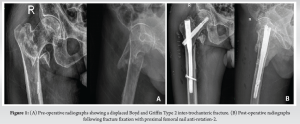

An 80-year-old male presented to our emergency department with a history of a slip and fall at his residence. Following this, he had pain in the right groin and was not able to bear weight on his right lower limb. On examination, the limb was shortened and externally rotated. There was fullness over the right groin, right hip, and greater trochanter, which were tender with restricted hip movements. Radiographs showed Boyd and Griffin Type 2 intertrochanteric fracture with medially displaced lesser trochanter, flexed proximal fragment, adducted, and proximally migrated distal fragment (Fig. 1).

The patient underwent closed reduction and internal fixation with short proximal femoral nail anti-rotation (PFNA-2). Intraoperatively, the reduction was achieved by manipulation of the flexed and adducted proximal fragment with the help of a bone lever (Fig. 1). Intraoperative and post-operative periods were uneventful. The patient was discharged on post-operative day 6, the surgical wound healed, sutures were removed on post-operative day 15, and the patient was mobilized with partial weight bearing with walker support. The patient presented to us again on post-operative day 21 with complaints of pain and swelling over the right thigh. There was no history of fever or re-trauma, and the patient was able to walk full weight bearing with walker support. There was a pitting type of edema in his right lower limb extending up to the right proximal thigh. There was diffuse fullness over the anterior aspect of the thigh, which was more prominent on quadriceps contraction. All the peripheral pulses were well felt, there was no calf tenderness, and no neurological deficits. High-resolution ultrasonography showed a well-defined hetero-echoic collection in the proximal thigh in anterior and medial aspect with central anechoic area probably communicating to the femoral artery measuring 6.2 × 6.9 × 10.2 cm and showing Yin–Yan sign in color Doppler suggestive of pseudoaneurysm with peripheral thrombosis (Fig. 2). The computed tomography (CT) angiography of the right lower limb showed a well-defined contrast filled saccular outpouching with smooth surface seen arising from posterior wall of proximal portion of profunda femoris artery distal to common femoral artery bifurcation. There was no evidence of thrombus within the outpouching. Surrounding organized hematoma noted in the anterior and medial aspect of the thigh, approximately measuring 6.5 × 8.5 × 14 cm, suggestive of pseudoaneurysm of the right profunda femoris artery (Fig. 2).